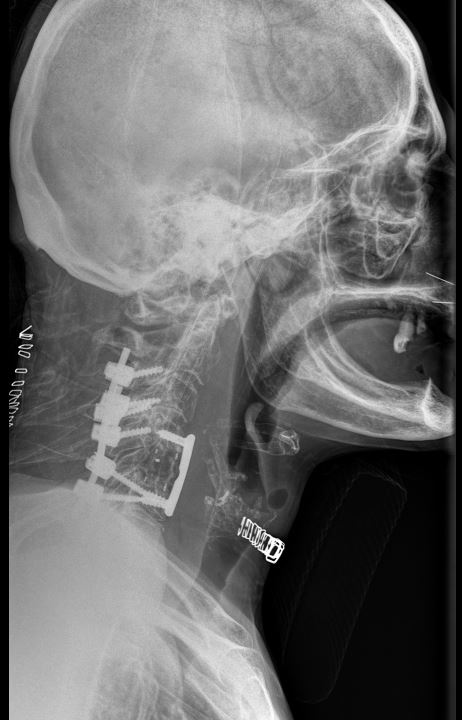

Πρόσθια – Οπίσθια (360ο) Σπονδυλοδεσία Αυχενικής Μοίρας Σπονδυλικής Στήλης